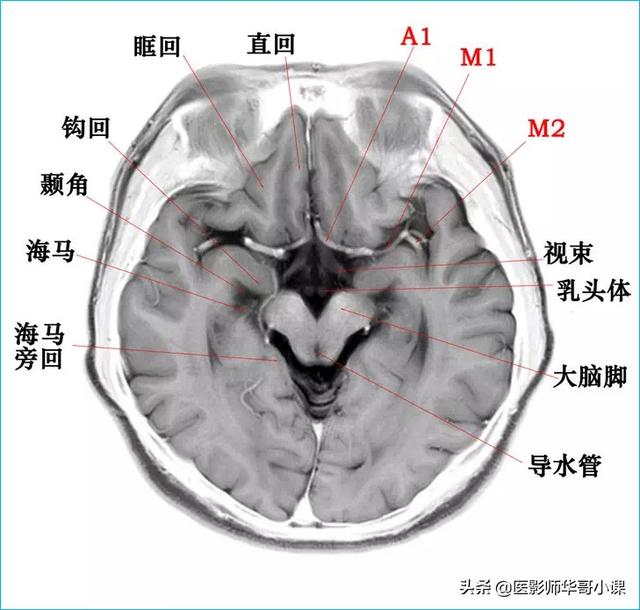

颅脑主要包括大脑、小脑、脑干、间脑,其中大脑又称为端脑,是人体的司令部,管辖人体的躯体活动、精神活动以及感觉行为等;脑干和小脑位于后颅窝的位置,脑干自上而下分为中脑、脑桥、延髓,脑干又称为生命中枢,对人体非常重要,因为脑干具有管辖呼吸和循环的初级生命中枢。其中大脑分为5个脑叶,分别是额叶、顶叶、颞叶、枕叶以及内侧面的岛叶。间脑分为上丘脑、下丘脑、后丘脑、背侧丘脑和底丘脑,背侧丘脑是一个重要的结构,是感觉传导路的重要中继站。颅脑包括颅骨和颅骨内的脑组织。颅骨由顶骨,颞骨,枕骨,额骨,以及颅底骨构成。颅骨构成的颅腔主要作用是保护脑组织。颅内的脑组织主要包括大脑,小脑,脑干。表面覆盖有软脑膜和硬脑膜,大脑分为左右两侧大脑半球,根据解剖位置又分为颞叶,枕叶,顶叶,额叶,各脑叶功能不尽相同。小脑也分左右半球。脑干分为延髓,脑桥和中脑三部分。